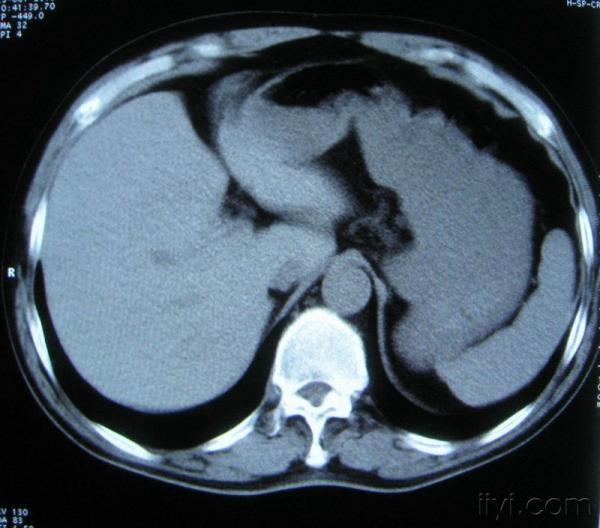

男。60岁,胸片示支气管炎治疗后复查CT。

你指那个肯定是淋巴结,中央系坏死,这很常见,特别在双侧腹股沟会经常看到。这个双侧腋窝及纵隔见多发小淋巴结征。

根据位置考虑应该是淋巴结,密度不均,是因为肿大的淋巴结中心液化坏死